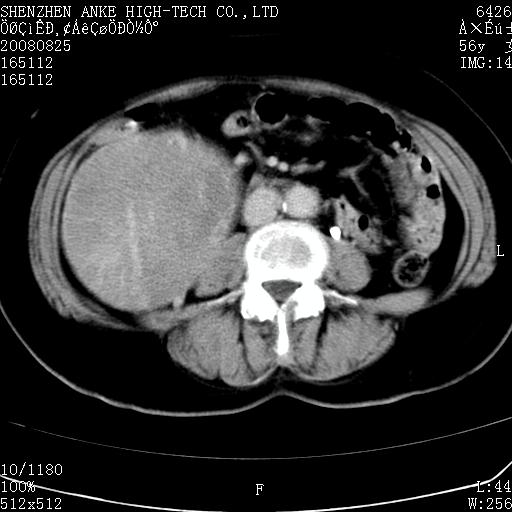

患者,女性,56岁,腰痛3年,查:右腹部约8x10cm肿块,固定,无压痛;8月23日在外院做了平扫,发现右肾巨大肿块(外院具体诊断不祥);今天在我院做了静脉肾盂造影,示:右肾明显增大,分泌功能明显减弱。

右肾癌可能大。

右肾癌

右肾癌可能性大.

右肾占位、癌可能性大。

支持右巨大肾癌。

1)考虑右肾癌并右肾静脉瘤栓形成。2)脂肪肝。

右肾癌可能性大。

右肾癌性变。

考虑右肾癌可能性。